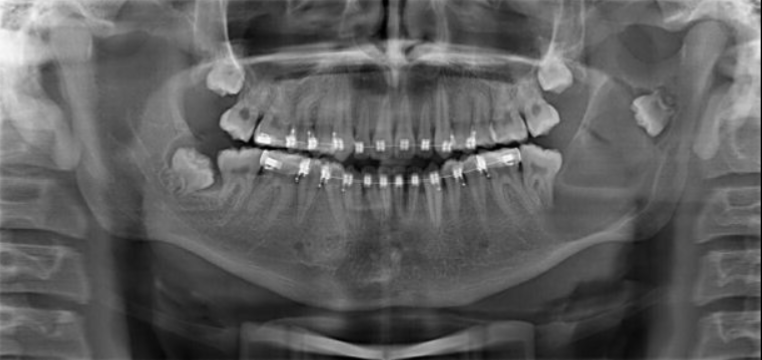

Describe the radiographic features of this Buccal Bifurcation Cyst?

Buccal Bifurcation of Molars

Roots Displaced Lingually

Occlusal Plane Inclined Buccally

Lingual Cusp Higher on BWs and PAs